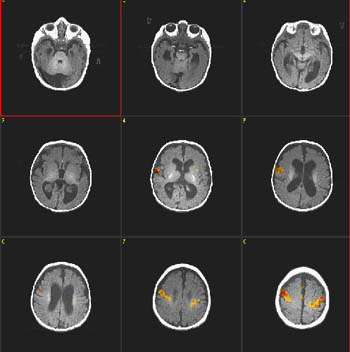

T1 weighted MRI

Transverse image at the level of the planum temporale. The left hemisphere is seen in the right side (radiological convention). The subject's task was listening to a story.The red bubble seen on the left side corresponds to areas related to complex semantic processing.

Functional MRI is based on small signal changes that result from the following cascade of events. A task elicits activation in one or several brain areas. These areas increase their metabolic demands, suffer vasodilatation, and alter their levels of deoxyhemoglobin and oxyhemoglobin. Since deoxyhemoglobin is a paramagnetic molecule, it influences the phase of local proton-spins, altering the source signal that is converted into images. Therefore, the image is a representation of local changes of levels of deoxyhemoglobin, related to the brain region performing a task.